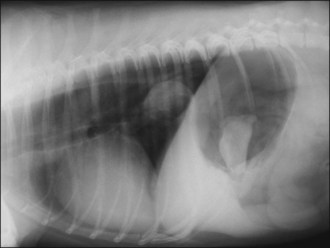

Plain thoracic radiographs (typically right lateral and dorsoventral (or left lateral) views) are useful in animals with regurgitation and may help to identify megaoesophagus, radiopaque oesophageal foreign bodies, aspiration pneumonia and mediastinal masses (Figures 22.1-22.3).

Figure 22.2 Right lateral thoracic radiograph in a dog showing a distal oesophageal foreign body (bone). Oesophageal dilation is present and a bone is also visible in the stomach.

Diagnostic imaging

In the author’s experience, the vast majority of oesophageal foreign bodies are radiopaque enough to be detected on plain radiographs; however, occasionally contrast radiography or endoscopy is required. The most common site of foreign body entrapment is the caudal oesophagus between the heart base and the cardiac sphincter (see Figure 22.2). In addition to the foreign body itself, plain radiographs often demonstrate increased soft tissue density around the foreign body and air in the oesophagus.

Plain radiographs are also useful to exclude pneumomediastinum (and possible pneumothorax) as a result of oesophageal rupture, and to identify evidence of aspiration pneumonia.